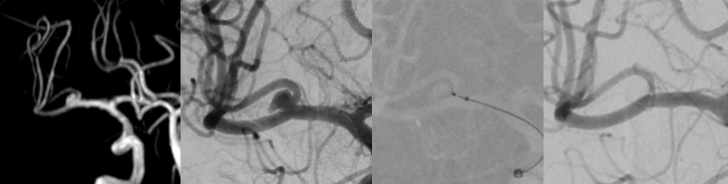

Diagnostically and therapeutically, the most modern methods and equipment are available for our patients. In addition to diagnostic neuroradiology, our clinic is characterized by a high level of expertise in minimally invasive neuroradiological therapy, both in the emergency treatment of strokes and in the elective treatment of aneurysms, vascular stenoses and vascular malformations.